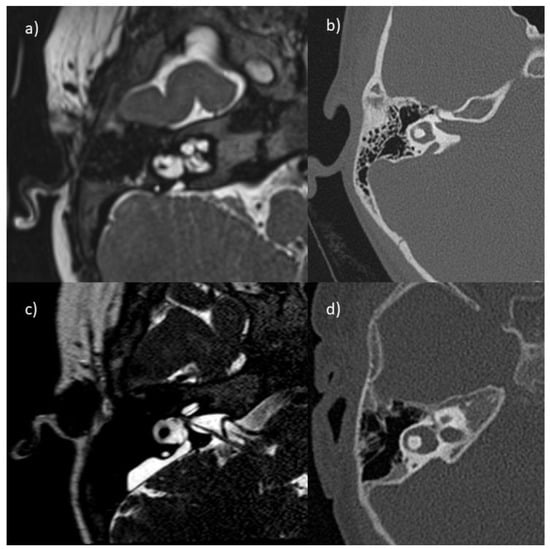

2.2.1. Radiological Exam